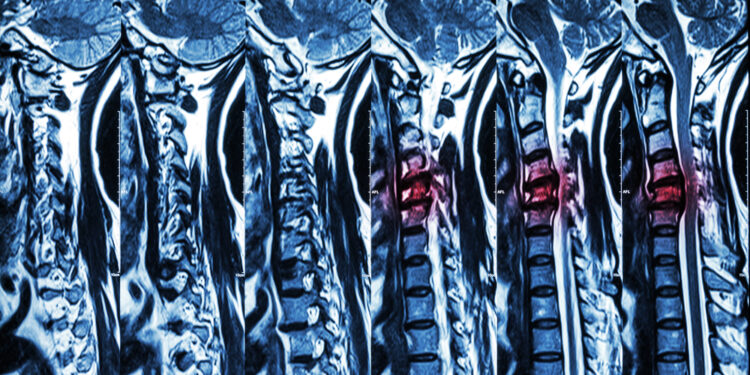

Diagnozei patikslinti skiriami vaizdiniai tyrimai:

- Stuburo rentgenograma

- Magnetinio rezonanso tomografija (MRT)

- Kompiuterinė tomografija (KT)

- Mielograma